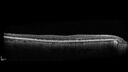

84 year old female The patient had cardiac stents done a week ago. Her stent was done late in the day. She did not notice anything that night but the next morning she noticed that it looked like there was steam coming out of the vent in the ceiling and like there was moister on the mirror. After that her vision changed to look like there was smoke inside her eye. This is more on the left eye than the right eye. Medical Hx: Influenza Immunization Not Received. Pneumococcal Vaccine Not Received. Diabetes Mellitus. Heart attack (2/23/2024). Hypertension, Systemic. Hyperlipidemia. Surgical Hx: Heart Stent (2/23/2024). Hysterectomy. Systemic Meds: Aspirin 81 mg. linaglitin. Metoprolol. NITROGLYCERIN. Ticagrelor. VALSARTAN. VA OD: Dcc20/32 Ncc20/200 VA OS: NccJ16 IOP: TP: OD:11 OS:10

reticular-drusen_119305_052424_04.jpg

Reticular pseudodrusen87 views00000